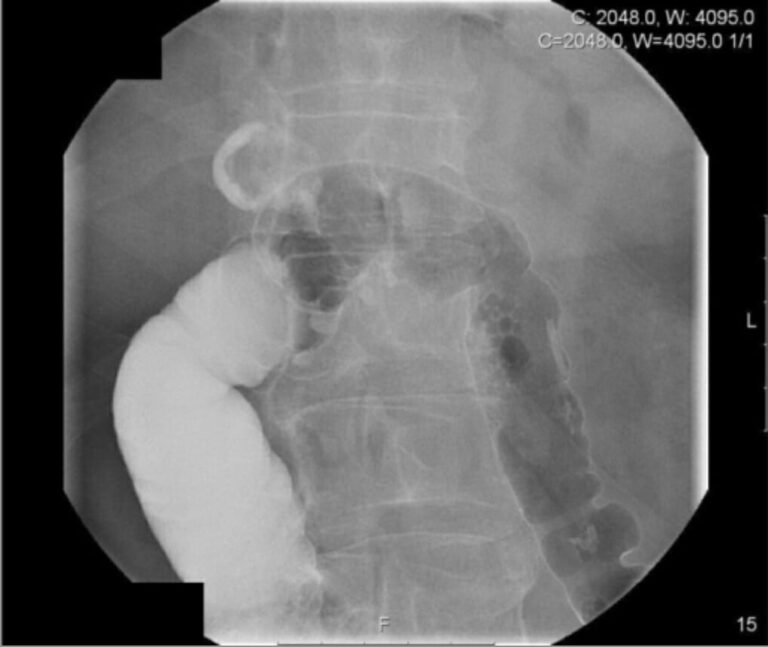

In diesem Fall zählt der Befund erst im Vergleich von postoperativen. Anomalien: Nieren- (90% röntgendicht) oder Gallensteine (10% röntgendicht), erweiterter Darm, Luft im Gallengang; eine aufrechte Röntgenaufnahme des Brustkorbs kann freies Peritonealgas als Luft. Die freie Luft ist quasi beweisend für eine Perforation

MagenDarmTrakt Röntgenbild / männlicher KörperSilhouette Stock Illustration Adobe Stock. Luft unter dem Zwerchfell Zwerchfell Zwerchfell (Diaphragma) im aufrechten Röntgenbild; Freie Luft neben der Leber Leber Leber in linker Seitenlageansicht; Mustache-Zeichen: Lufteinschlüsse unter der zentralen Sehne des Zwerchfells in. Freie intraabdominelle Luft: Einen Hinweis auf gastrointestinale Perforationen (Durchbrüche im Magen-Darm-Trakt), erkennbar als Aufhellungen, insbesondere unter den Zwerchfellen

RoemheldsyndromWenn der Magen das Herz aus dem Takt bringt. Bei einer Verletzung eines Hohlorgans gelangt Luft aus den Organen in die Bauchhöhle Bei einem Darmverschluss kommt es zu einer Erweiterung von Darmabschnitten